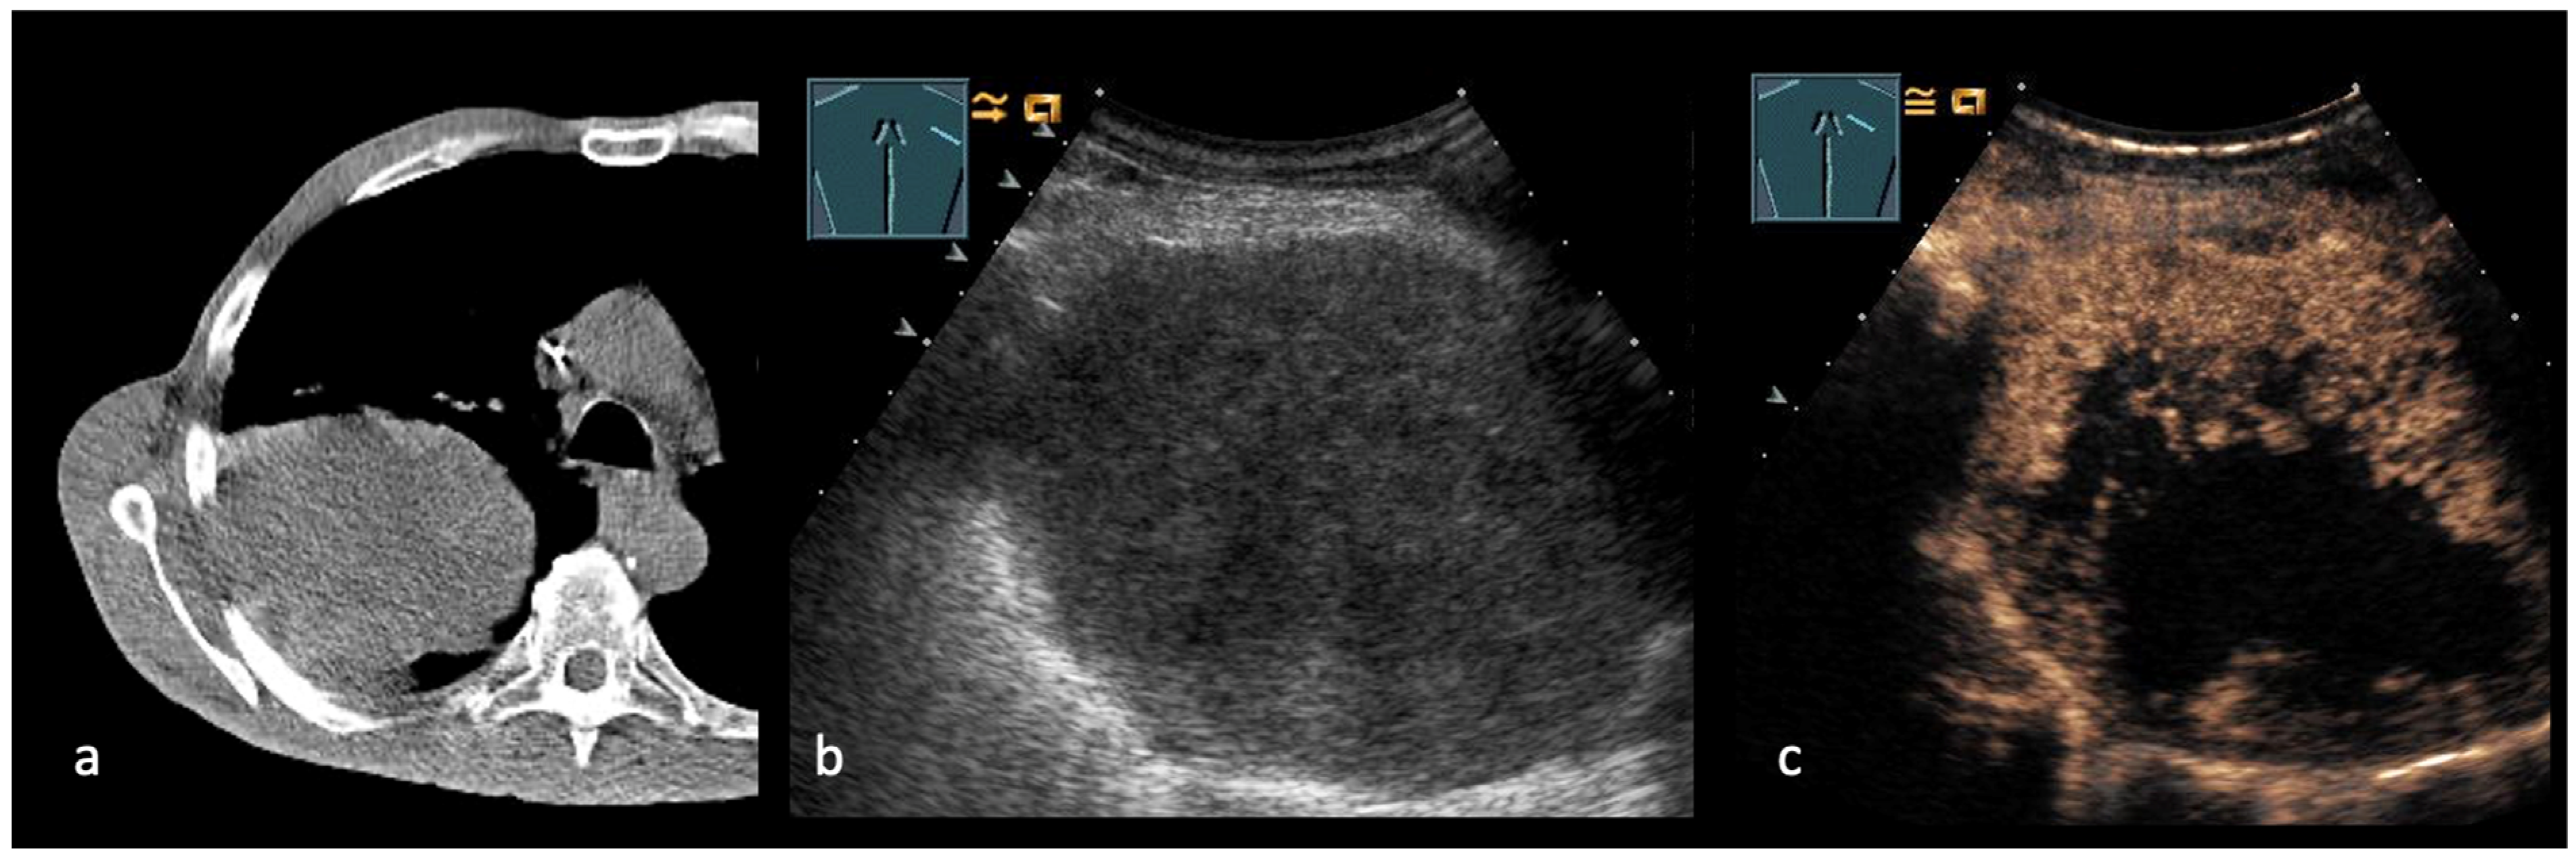

5. Transcutaneous Ultrasound in the Evaluation Distant Metastasis